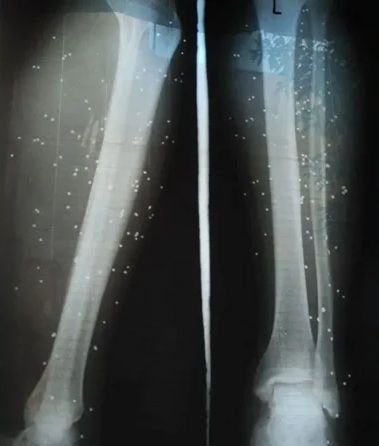

عکس رادیولوژی پای تارا؛ پزشک به او گفته است این ساچمهها مثل ترکشهای جنگ در بدنش میماندبی بی سی: سروش پاکزادهشدار: این مطلب حاوی جزئیاتی است که ممکن است آزارنده باشد.

چند روز بعد یک جراح متخصص چند ساچمه را از بدنش خارج کرد. ولی به او گفت که: «اینها هم مثل ترکشهای زمان جنگ است، نمیشود درشان آورد و در بدن میماند.»

تصویر زخم ساچمهها روی پای تارا؛ دهها نقطه سیاهرنگ محل ورود ساچمه به بدن را نشان میدهداستفاده ماموران از تیر جنگی، باعث شده که درمان معترضانی که زخمشان عمیق است، در خانهها ممکن نباشد.نیما در تهران جراح است. او به بیبیسی گفت روز فراخوان، جلوی خانهاش شاهد زخمی شدن جوانهای زیادی بوده است: «یکی از مجروحها را گذاشتم داخل صندوق عقب ماشینم تا با خودم ببرمش به بیمارستان. اگر میگذاشتمش صندلی عقب، ممکن بود در مسیر دستگیرمان کنند.» نیما میگوید ماموران مسلح جلویش را گرفتند و بعد از دیدن کارت شناسایی بیمارستان، اجازه دادند به مسیرش ادامه بدهد.